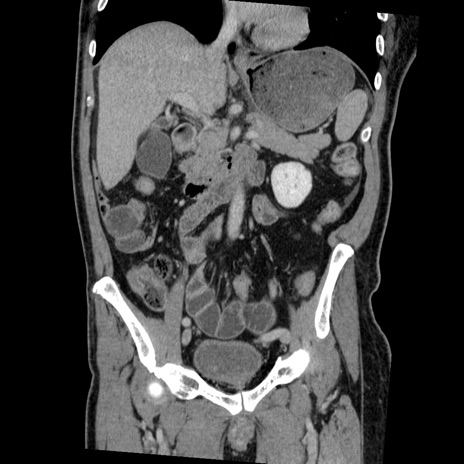

症例22(冠状断像)

【症例】50歳代男性

【主訴】腹痛

【現病歴】AVMからの被殻出血のため回復期リハ病棟入院中。 本日午後3時頃急に下腹部痛が出現した。

【既往歴】AVM、被殻出血、虫垂炎、高血圧

【身体所見】意識晴明、左半身不全麻痺、会話の理解は良好、36.5°C、腹部:膨隆、全体に板状硬、下腹部正中に圧痛点あり、反跳痛-、筋性防御不明、右下腹部にope scar

【データ】WBC 9400、CRP 0.06